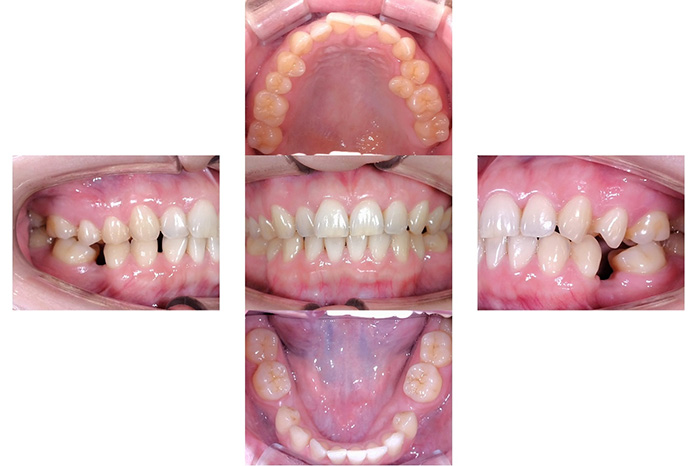

前歯の見た目と噛み合わせのバランスを整えたケース

「前歯が強くかみ込んでいる気がする」「歯並びだけでなく、噛み合わせも気になる」

このようなお悩みでご相談いただくことがあります。

今回の患者様は、ディープバイト(過蓋咬合)による前歯の見た目と噛み合わせを気にされて来院されました。ディープバイトとは、上の前歯が下の前歯に深く重なっている噛み合わせのことで、見た目の問題だけでなく、前歯や顎への負担につながることがあります。

本症例では、マウスピース型矯正装置(インビザライン)を用いて治療を行いました。合計84枚のアライナーを使用し、歯並びだけでなく咬合の深さにも配慮しながら治療を進めました。

治療後は、前歯の見た目のバランスが整い、噛み合わせも改善しました。

当院では、見た目を整えるだけではなく、治療後の噛み合わせまで考慮した矯正治療を大切にしています。